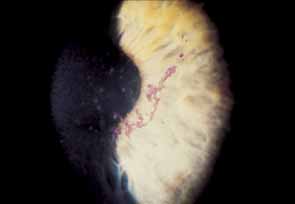

Ocular manifestations of varicella infection include epibulbar conjunctival or limbal corneal “pocks” (round, focal accumulations of inflammatory cells, lymphocytes and neutrophils), punctate keratitis, nonherpetic dendriform keratitis, nummular keratitis, disciform keratitis or keratouveitis (Fig. 2).7,25–32 Rarely, varicella has been associated with gangrene of the eyelids, interstitial keratitis, progressive corneal ulceration (“melting”), extraocular muscle palsies, internal ophthalmoplegia, cataract, uveitis, retinopathy, or optic neuritis.26,28,33–40 Infants born with varicella (congenital varicella syndrome) can manifest microphthalmos, chorioretinitis, cataracts, microcephaly, deafness, and cardiac anomalies.28,41

Fig. 2 Varicella nummular keratitis (same patient as in Fig. 1).

Epibulbar pocks occur most often during active systemic varicella and are suspected to harbor live virus. Pocks can also develop weeks or months after the systemic disease, at which time they probably represent a sterile, phlyctenule-like, cell-mediated immunologic reaction to retained viral antigen (but not the live virus). In either case, the pocks persist for 1 to 2 weeks and then resolve spontaneously. These conjunctival lesions are visually insignificant, but corneal pocks can leave scarring and vascularization. Varicella pocks are can be treated empirically with a topical antiviral agent such as trifluridine or simply observed. Pocks that develop later respond to short-term pulsed topical corticosteroid therapy.